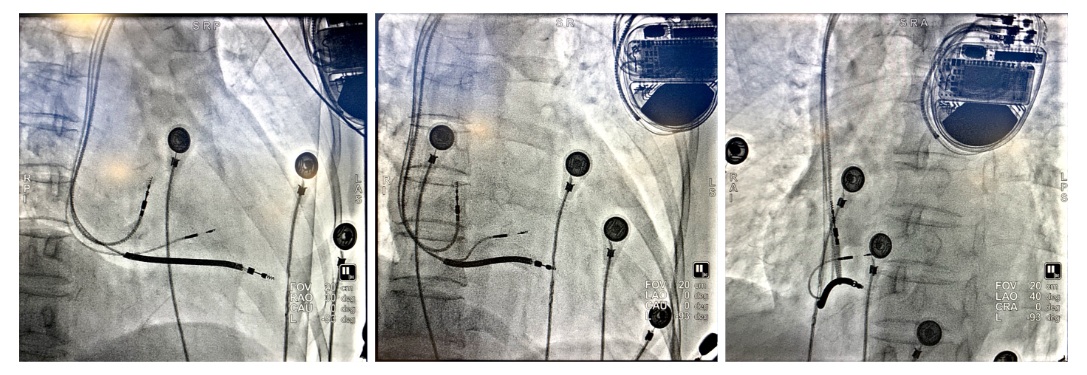

(上图从左到右分别为RAO 30°;AP;LAO 40°)